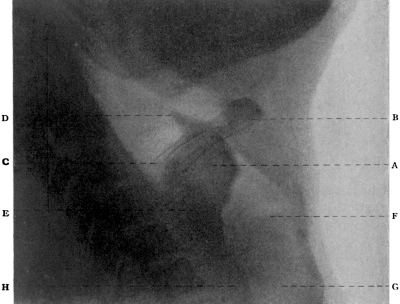

| 251. | Topography of the Auditory Region of the Skull | 462 |

| 252. | Exploration for a Temporo-sphenoidal Abscess | 463 |

| 253. | Exploration for a Cerebellar Abscess | 467 |